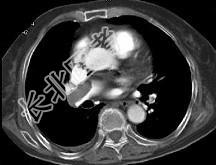

- 单项选择题82岁,女性, 突发右侧胸痛,呼吸急促, 行急诊CT检查,如图所示, 请选择最佳答案 ( )

D、肺动脉栓塞